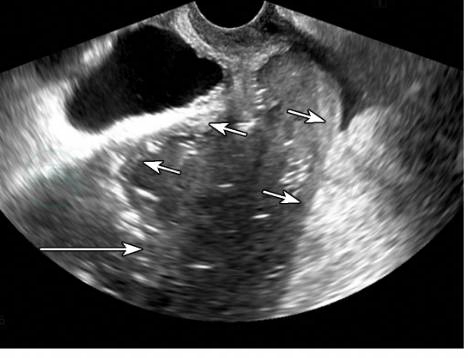

2.子宫积脓

子宫积脓时可见子宫呈球形增大,边界清晰,宫腔内呈液性,并伴有较多点状回声(图16-23)。

图16-23子宫积脓

子宫增大,宫腔积脓呈液性伴低弱回声及气体强回声(长箭头所示),宫壁薄(短箭头所示)。